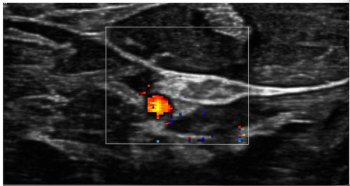

Ultrasound and MRI findings from a new study suggest that greater carotid atherosclerosis and elevated white matter hyperintensities among women with the APOEe4 genotype, a strong risk factor for Alzheimer’s disease, are associated with increased PTSD symptoms in midlife women.